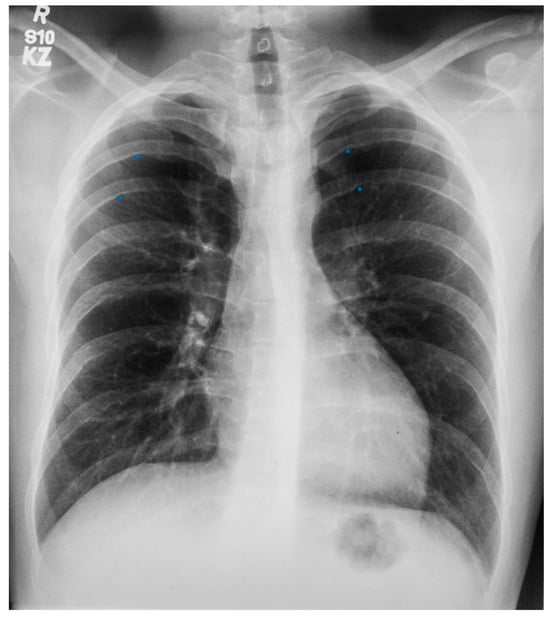

Figure 9.

Posteroanterior chest X-ray of sinus venosus atrial septal defect. This chest X-ray is of a 24-year-old female with a sinus venosus atrial septal defect and anomalous right upper pulmonary venous drainage to the superior vena cava. The image is well centered and there is a good inspiration. The cardiothoracic ratio is increased, the pulmonary artery segment is increased and the pulmonary vascularity is plethoric. Also note that there is a right-sided aortic arch (blue dots). This allows the enlarged pulmonary trunk to be better visualized because the thoracic aorta does not obscure it. Because she had dyspnea, fatigue and exercise intolerance she underwent surgical repair of the ASD and redirection of the right upper pulmonary vein to the left atrium. Her postoperative CXR showed decrease in C-T ratio and pulmonary vascularity. Her symptoms resolved.